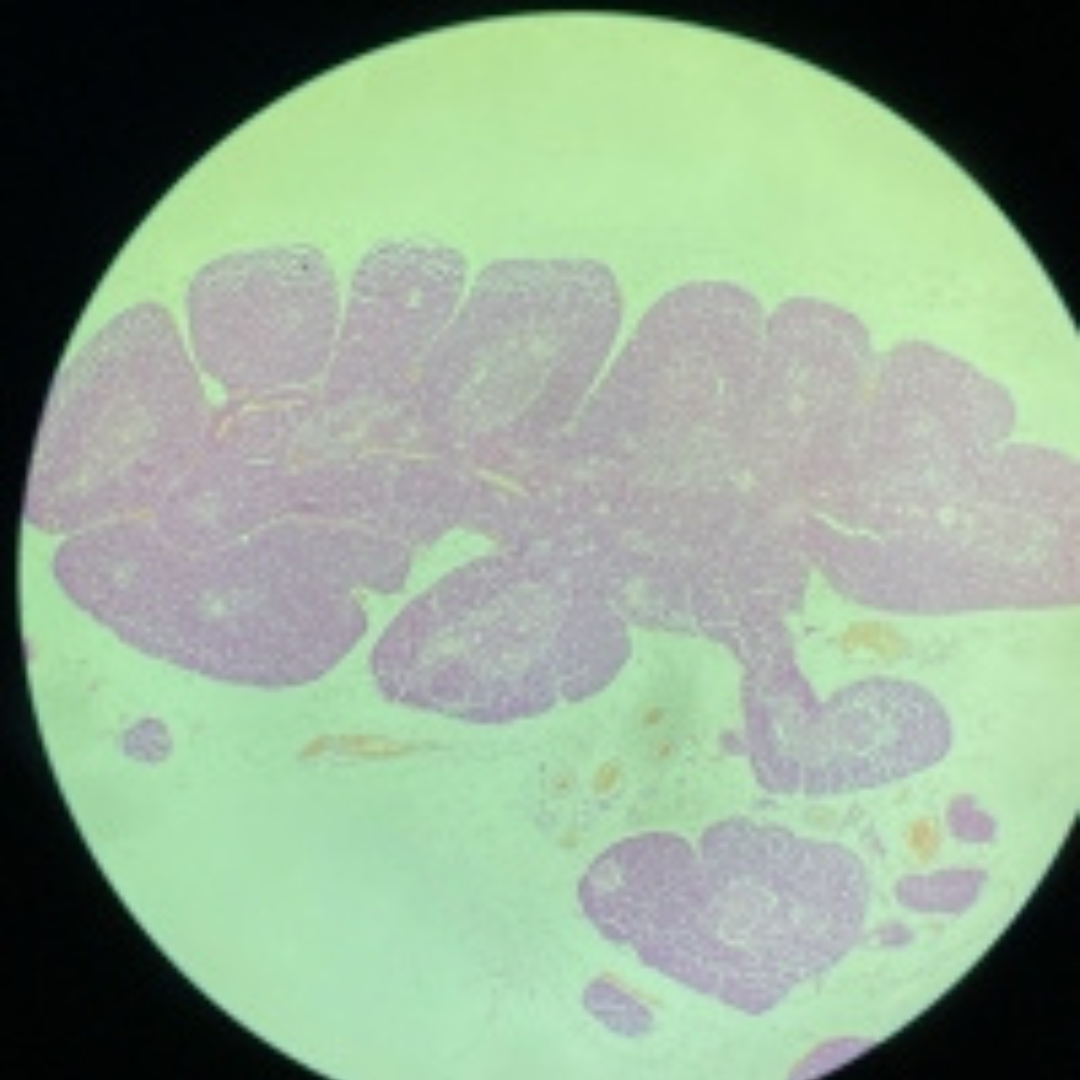

16

New cards

Tonsil

17

New cards

Tonsil

18

New cards

Tonsil

19

New cards

Tonsil